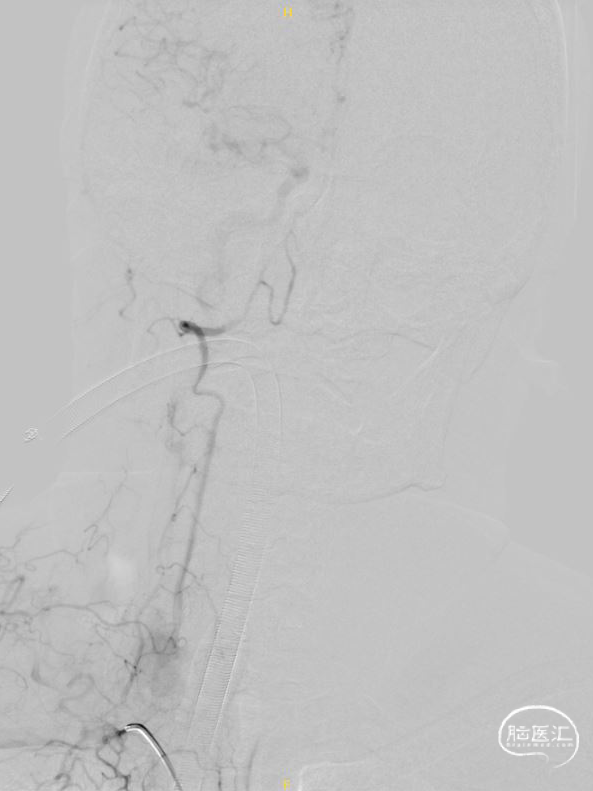

右椎正侧位造影提示:右椎止于小脑下后动脉。

左椎正侧位造影提示:血流缓慢,左椎起始部迂曲,BA下段重度狭窄。

超选左椎行3D旋转造影。

将8F 导引导管置于左侧锁骨下动脉,6F 115cm Navien中间导管置于左侧椎动脉V2段,调整工作角度,于路图下使用HYBRID 1214DA微导丝将SL-10微导管通过基底动脉狭窄段,并置于左侧大脑后动脉。

交换300cm Transend微导丝后,交换1.5*15mm Gateway球囊缓慢扩张。

交换3.0*15mm Wingspan支架,定位准确后释放,交换2.0*9mm Gateway球囊于支架内后扩张。

术后3D旋转造影。